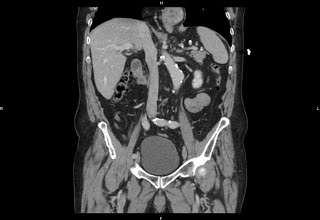

- un scanner